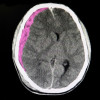

Sementara itu, traumatic brain injury on CT (TBI-CT) adalah cedera otak traumatik yang tampak pada gambaran CT, seperti perdarahan intrakranial, kontusio, edema serebral, infark traumatik, cedera akson diffuse, cedera shear, sigmoid sinus thrombosis, dan pergeseran midline atau herniasi. Contoh lain adalah pneumosefalus, fraktur depresi tengkorak selebar dasar tengkorak, dan diastasis tengkorak.[3,7]